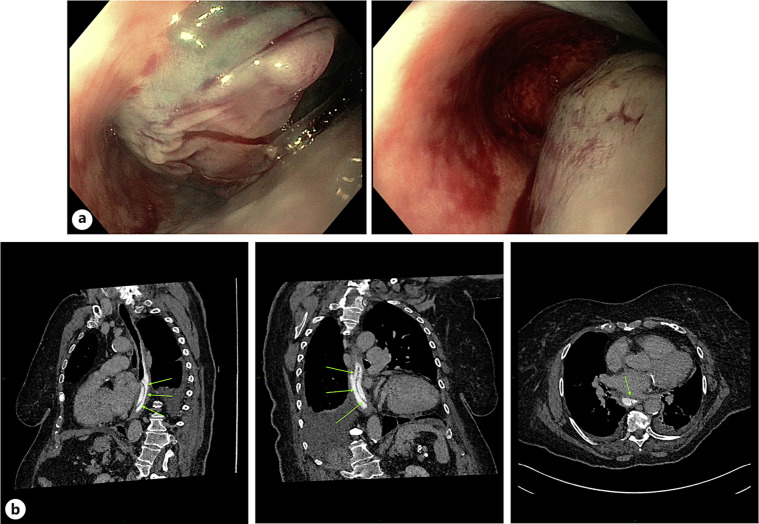

Case presentation: We present an unusual case of an 87-year-old woman on low dose aspirin who presented with severe chest pain and sudden onset of haematemesis without prior history of forceful vomiting or Valsalva manoeuvres. An emergency upper gastrointestinal endoscopy confirmed the initial diagnosis of a spontaneous intramural oesophageal haematoma and a follow up computed tomography scan of the chest confirmed the presence of an intramural oesophageal dissection.